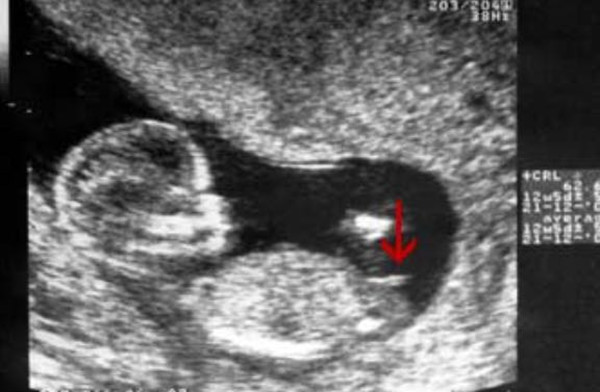

【怀孕妈妈知识宝典|nt图有三条线是怎么回事,和男女有关吗?】很多孕妈反映说自己在做nt时看到胎儿双腿间有圆圆的、尖尖的小东西 , 也有3个亮点的情况 , 医生给出的解释是可能这是男胎宝宝的生殖器官 。 如果胎儿双腿间看到的是三条线或者黑线的话 , 初步可以判定为女胎宝宝的外生殖器 , 也就是医学上说的女胎宝宝大小阴唇 。

但有的医生说 , 这个时候男胎和女胎的外生殖器差不多一致 , 如果不仔细区分的话 , 是看不出男女的 。 但有一条个说法大家可以确定 , 那就是如果是亮点和两个圆球的话 , 男孩的几率更大 , 如果是平平的 , 没有nub节点的 , 或者说大家看到的3条线一般女孩的几率更大 。